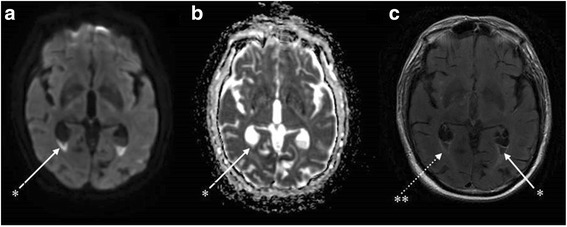

Fig. 1.

Brain magnetic resonance imaging (day 6) showing an aspect of ventriculitis in multiple axial sequences. *Irregular declivous intraventricular debris with restricted diffusion in the occipital horns with a moderate dilatation of the lateral ventricles seen in all sequences: diffusion (a), apparent diffusion coefficient (b) and T2 fluid attenuated inversion recovery (FLAIR) gadolinium (1c). **Periventricular hyperintensities and ependymal enhancement in the axial T2 FLAIR with gadolinium enhancement sequence (c)

The patient’s neurological state progressively improved to regain a vigilant state and was extubated on day 5 of antibiotic therapy. He was discharged to the infectious diseases unit. Nonetheless, he remained confused and somnolent (Glasgow coma score 14/15). Magnetic resonance imaging (MRI) with T2 fluid-attenuated inversion recovery (FLAIR) sequences performed on day 6 revealed the presence of a declivous purulent material inside the lateral ventricles with a moderate dilatation of these structures, not requiring any drainage (fig. 1). This material showed restricted diffusion (decreased apparent diffusion coefficient [ADC] value) and no magnetic susceptibility artefacts on T2* sequences, ruling out the possibility of a blood sediment. It also revealed punctiform hyper intensities in T2 weighted sequences and b1000 diffusion-weighted imaging (DWI) in multiple vascular territories with cortical and deep white matter distribution. These lesions were characterised by a normal or decreased ADC value and some of them were enhanced after gadolinium injection (fig. 2). All of these findings were consistent with semi-recent ischemic strokes.